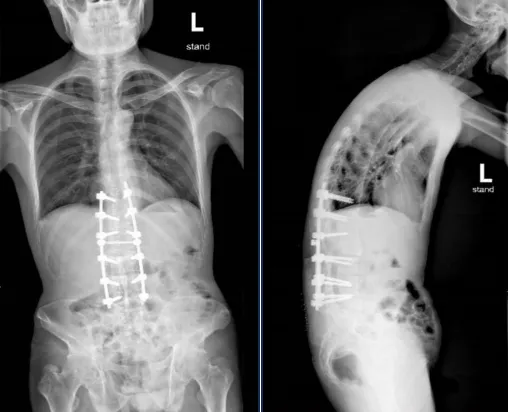

▲患者术前术后对比

经过小妲己直播app 骨科团队与万勇教授团队的连续奋战、攻坚克难,方师傅的手术顺利完成,脊柱畸形程度得到明显改善。术后,小妲己直播app 骨科护理团队为方师傅的术后康复制定了周密的护理计划,从营养管理、术后康复、疼痛管理等方面入手,全方位为患者康复保驾护航。经过精治疗,患者在术后第5天在佩戴肢具后独立下床行走。“折叠人”的腰杆,挺直了!

▲患者手术前脊柱正、侧位片

▲患者手术后脊柱正、侧位片